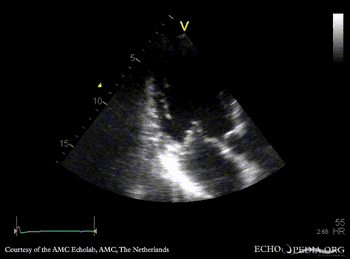

| PSAX: thickend mitral valve leaflets, prolaps of PMVL